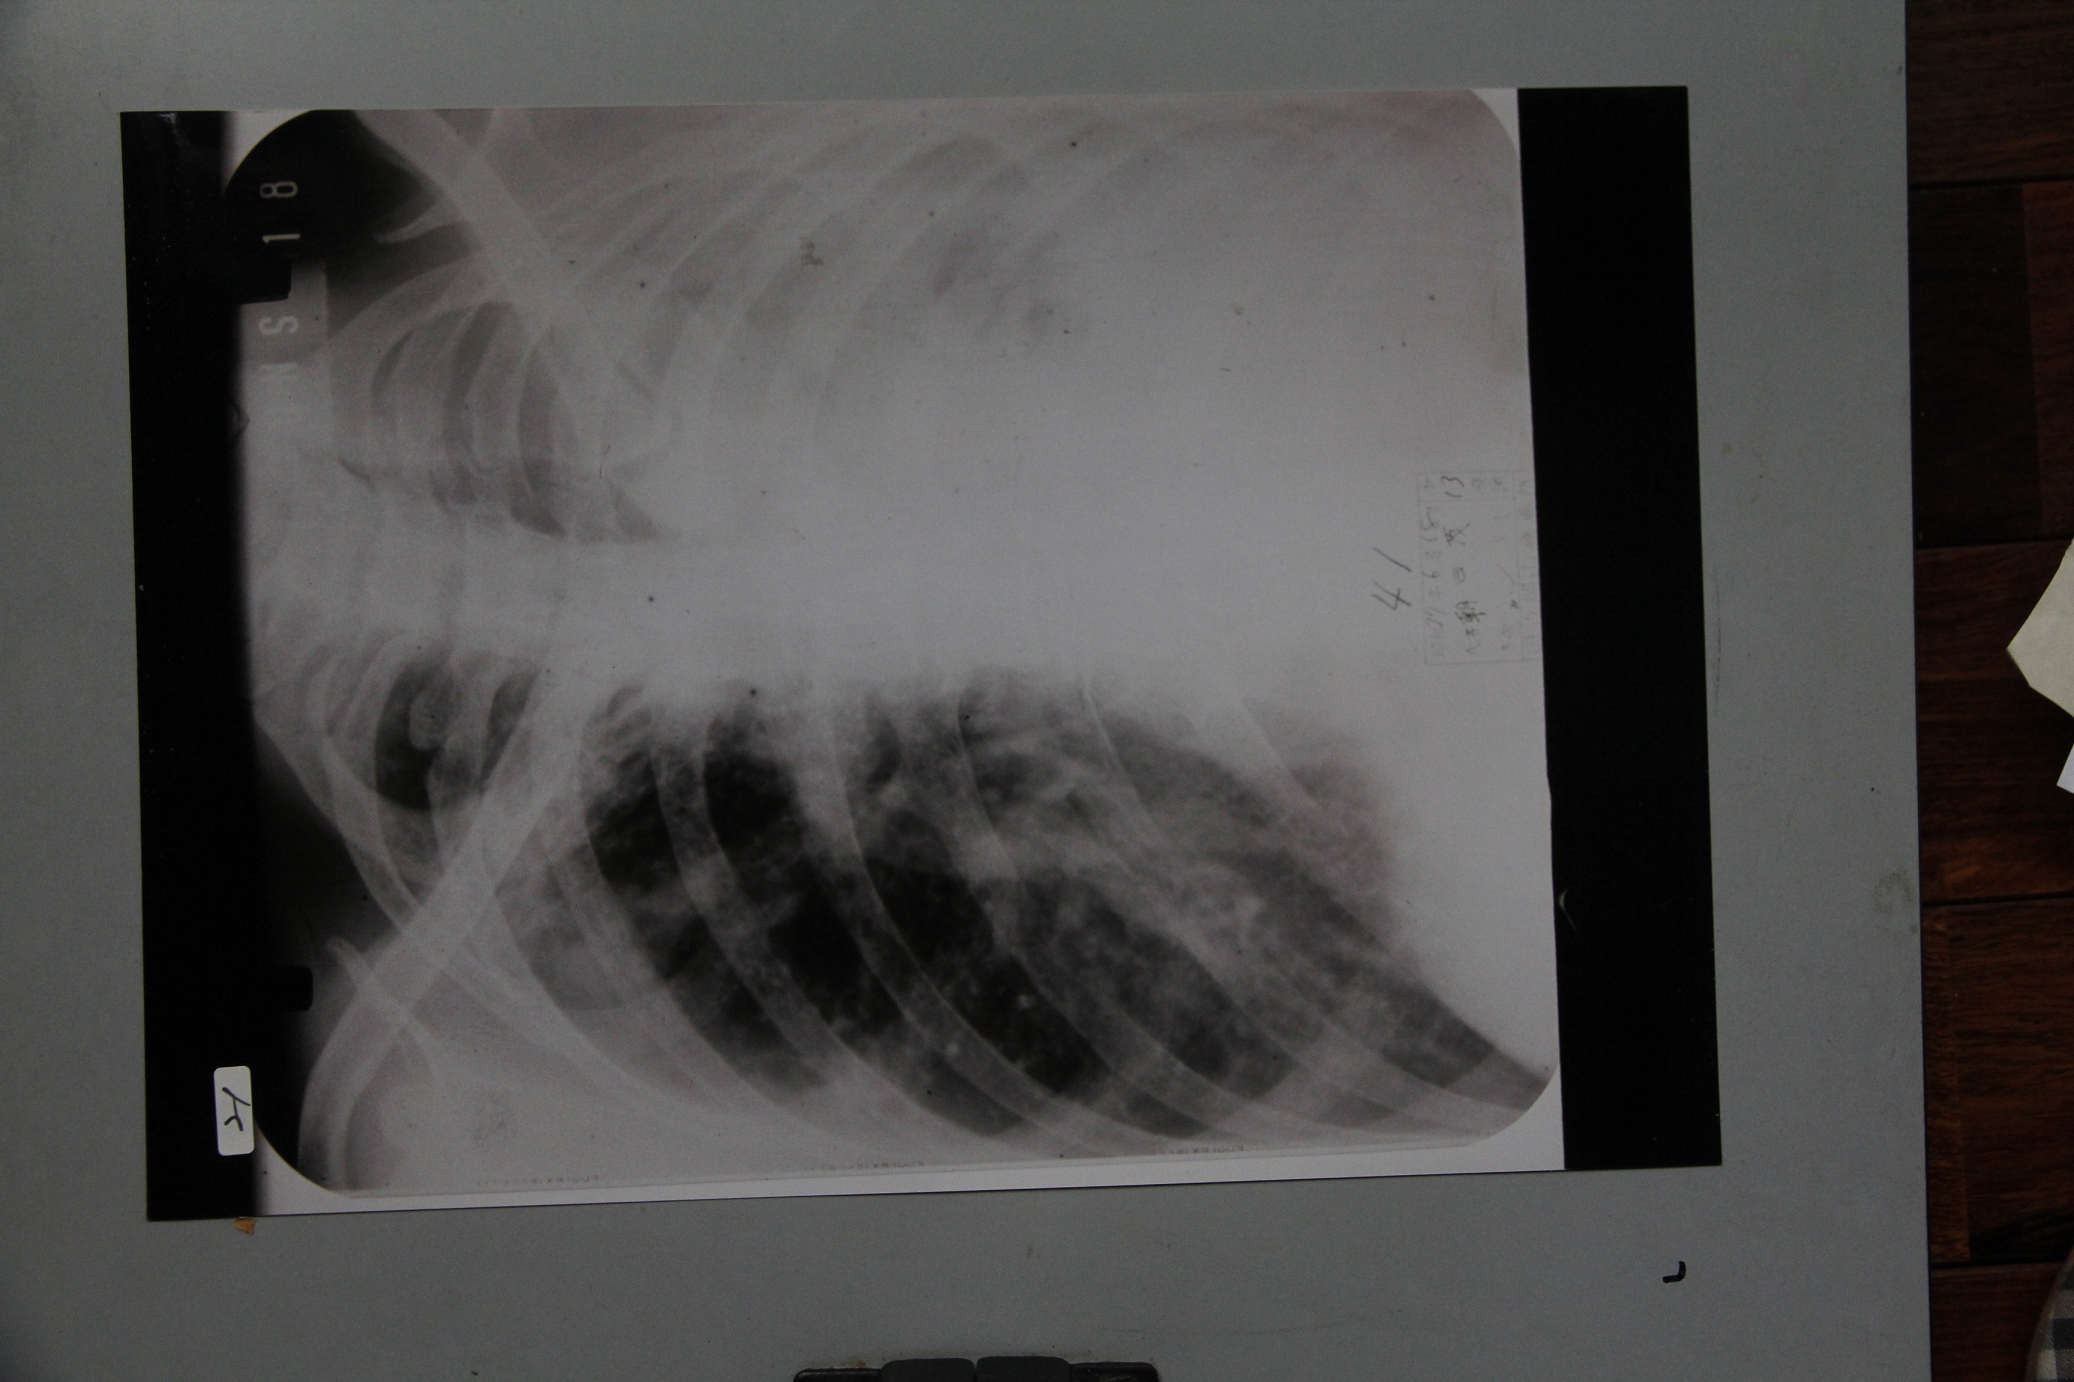

朝日茂胸部レントゲン写真

遺品コード: 21 | 作成日時: | 作成者:

朝日茂胸部X線写真